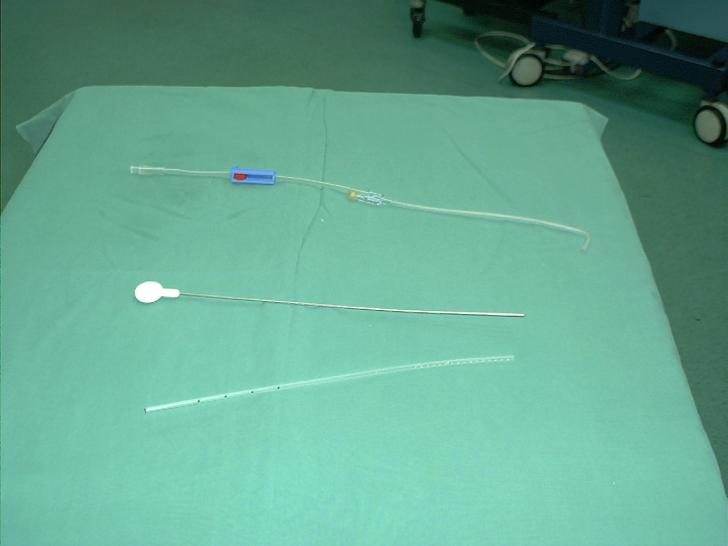

Traumatisme si leziuni

Traumatism abdominal inchis Trusa de lavaj peritoneal Citeste tot ... 951 cuvinte

Dimensiune mica

+ cu imagini |